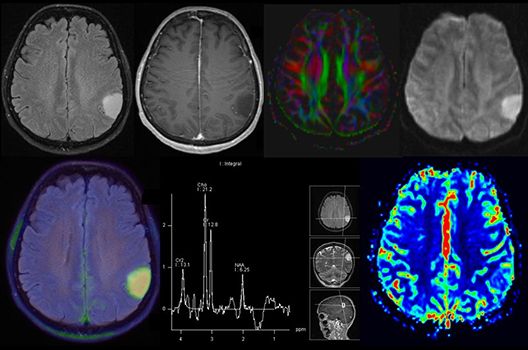

Onkologische und Hybridbildgebung

- PET/MRT in der Neuroonkologie

- Diffusion Kurtosis Imaging

Die Hybridbildgebung mittels PET/MRT spielt insbesondere in der onkologischen Bildgebung eine wichtige Rolle. Eine mögliche Fragestellung ist die Unterscheidung zwischen einem Tumorrezidiv oder therapeutisch assoziierten Veränderungen insbesondere dann, wenn diese Frage mittels MRT alleine nicht beantwortet werden kann.

Die bildgebende Diagnostik und Verlaufsbeurteilung von Tumoren des Nervensystems ist einer der klinischen und Forschungsschwerpunkte unserer Abteilung. Eine besondere Bedeutung kommt der Hybrid-Bildgebung zu. Das Universitätsklinikum verfügt über einen integrierten Ganzkörper-PET/MRT-Scanner, der die Vorteile der MRT-Bildgebung und der Positronenemissionstherapie (PET) vereinigt. Aufgrund der langjährigen klinischen Arbeit und Forschungstätigkeit mit diesem Gerät hat die Neuroradiologie Tübingen maßgeblich zur Etablierung dieses Verfahrens beigetragen. Auch weiterhin forschen wir intensiv an neuen Methoden zur frühen Einordnung von Tumoren und insbesondere Tumorrezidiven, die mit anderen Methoden häufig nicht erfasst werden können.